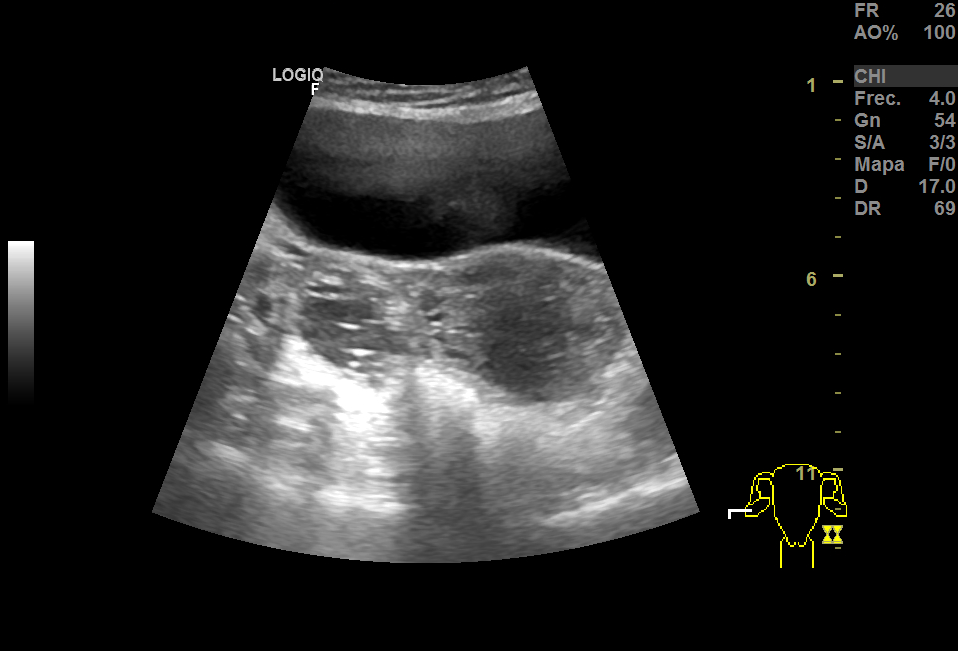

Realizamos una ecografía en el centro de salud y objetivamos, adyacente a útero, una imagen heterogénea de gran tamaño (15x8 cm), con vascularización, que podría corresponder a un mioma gigante. En anejo derecho, imagen redondeada de aproximadamente 3 cm en cuyo interior aparecen líneas hiperecogénicas en un fondo hipoecoico que podrían corresponder a teratoma, sin descartar otra patología. Ante la duda, derivamos a ginecología.

En ginecología, repiten ecografía, esta vez transrectal (paciente sin RS). Confirman mioma de gran tamaño y masa anexial bilateral, por filiar.

La RMN confirma la masa fibrótica de 11x8x10 en relación con mioma pediculado. Imágenes en la línea medida de fondo saco de Douglas de 55x46 y otra de 37x36, bien delimitadas, hiperintensas, compatibles con teratomas.